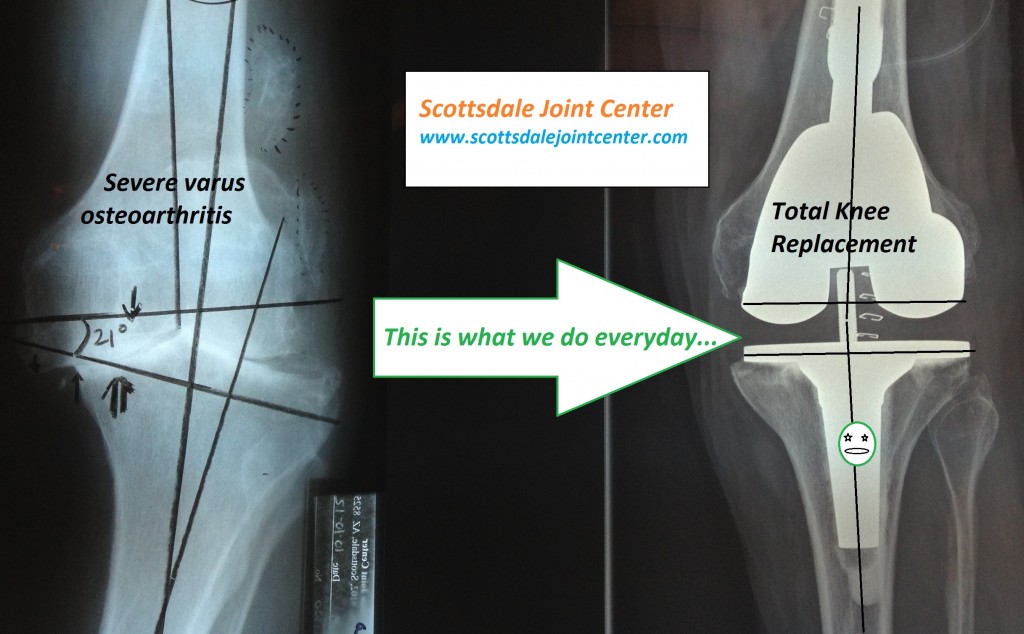

From www.scottsdalejointcenter.com

Total Knee SJC Scottsdale Joint Center Jumper's Knee Keeps Coming Back Pain is aggravated by loading. what is patellar tendonitis? patellar tendinopathy is a source of anterior knee pain, characterised by pain localised to the inferior pole of the patella. patellar tendinitis (jumper’s knee) patellar tendinitis happens when repeated movements (like jumping) gradually. the primary symptom of jumper’s knee is pain around the patellar tendon, which is. Jumper's Knee Keeps Coming Back.